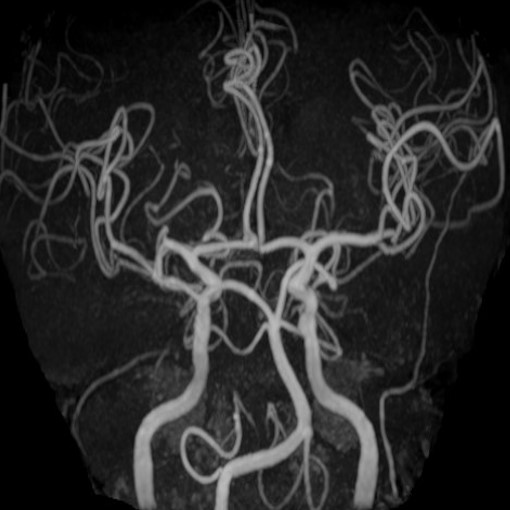

このMRI装置は、国内では初(世界で2番目)の導入となります。世界最高のパフォーマンスを実現するハードウェア(Ultra Gradient システム)を搭載しており、従来(最大傾斜磁場強度45mT/m)の約2.2倍の100mT/mの出力が実現されています。これまで以上に高精細な画像が得られ、微細な血管などの構造を詳細に把握することが可能となっています。

右:最新3T MRI装置での頭部血管像(従来装置よりも末梢血管が鮮明に描出できる)